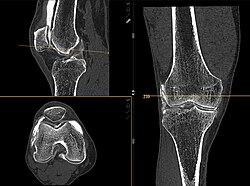

Multiplanare Reformation und 3D-Darstellungen

Erst mit der Einführung von Mehrzeilen-Spiral-CTs Mitte der 1990er Jahre gab es in der Computertomographie isotrope Voxel.[1] Da alle heutigen (2011) klinischen CTs kleine isotrope Voxel erzeugen können, ist eine hohe räumliche Auflösung in beliebigen Raumrichtungen möglich. Durch die multiplanare Reformation werden auch sagittale und koronale Darstellungen in hoher Qualität möglich, die für den Nicht-Radiologen erheblich einfacher zu verstehen sind. Die Maximum Intensitäts Projektion stellt die Maximalwerte aus einem frei wählbaren Datenvolumen dar, die auf eine Ebene projiziert werden, vergleichbar einem Schattenbild. Durch die heute auf Auswerte- bzw. PACS-Workstations preiswert verfügbare Rechenleistung können aus den Daten auch hochwertige 3D-Darstellungen in Form von MIP, Surface-Rendering oder – am aufwändigsten und beeindruckendsten – Raycasting erzeugt werden.

Für den Radiologen in der klinischen Routine ist die MIP zur Gefäßdarstellung und der Suche nach Lungenmetastasen sehr hilfreich. Eine 3D-Darstellung ist zur präoperativen Darstellung von Mehrfragment-Frakturen für den Chirurgen nützlich. Raytracing und MIP werden ferner im Rahmen von Spezialanwendungen für Visualisierungen in der Computertomographie des Herzens und der virtuellen Koloskopie verwendet.